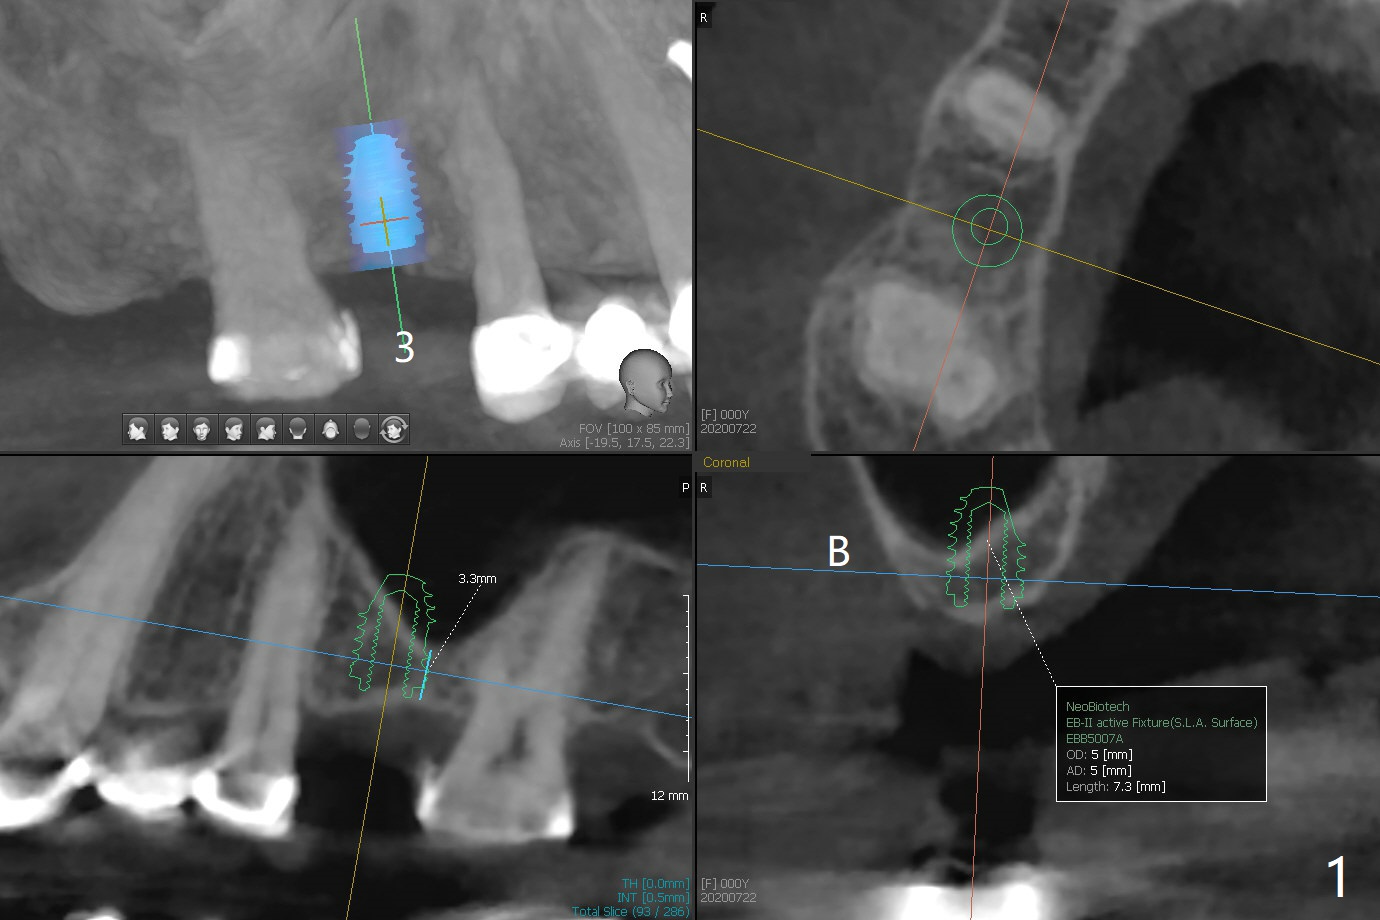

A 57-year-old woman requests implant at #3 after temporarization of #7-11 (UF implant at #11).  Due to several neighboring crowns, implant placement will be free hand with incision.  Check whether there is water lifter in the master kit.  Initial depth will be 4 mm (Fig.1).  Insert PRF membrane and sticky bone (a little).  Prepare more of not so sticky one when needed.  The average bone density of the osteotomy area is 700 units.  Take photos of #10 and 11 (no denture pressure mark or fistula) before procedure.  57岁女要求做右上六植牙